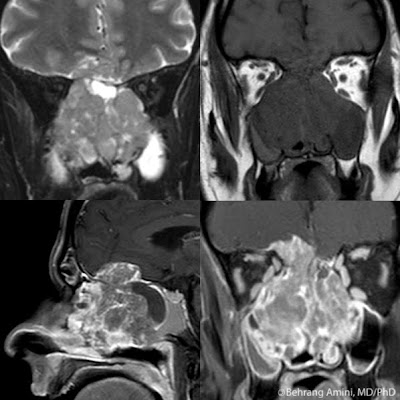

CTA is the modality of choice for this rare diagnosis. The aorta-superior mesenteric artery angle and the distance between the aorta and superior mesenteric artery, and the third portion of the duodenum can be assessed on CTA.

In normal patients, the aorta-superior mesenteric artery angle is between 25°-60°, and the aorta-superior mesenteric artery distance is between 10 mm - 28 mm.

Patients with superior mesenteric artery syndrome have angles between about 5° to 20° and aorta-superior meseteric artery distances between 2 mm and 8 mm.

In our patient, the aorta-superior mesenteric artery angle was about 15° and the aorta-superior mesenteric artery distance was about 5 mm.